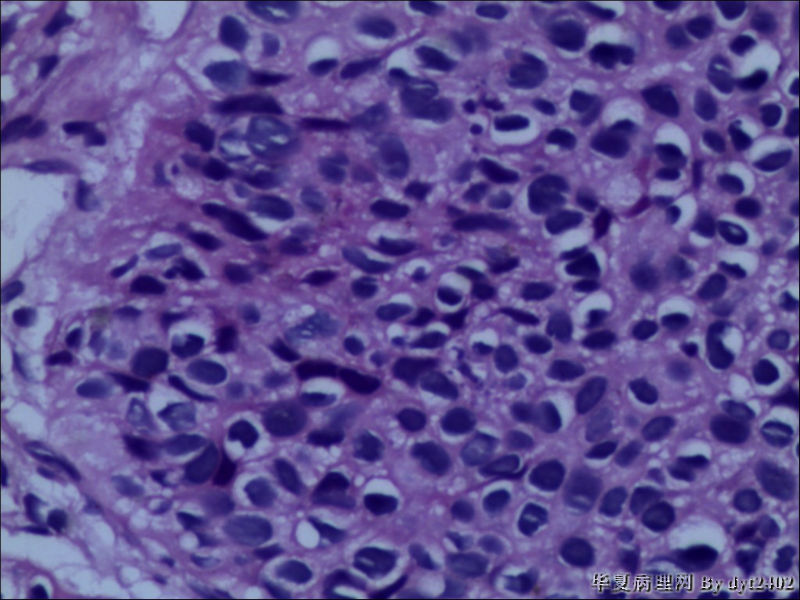

• 宫颈活检 其中一点较迷糊图1

图1

四点中三点是CIN iii,另一点怀疑有更重病变

这个病人是44岁,去年11月底阴道脱落细胞、TCT均见细胞异常,建议活检,病人犹豫,接着单位组织到外院体检时做阴道镜正常,后霉菌感染,此时宫颈未涂醋肉眼看还光滑,直至今年3月来做活检,事前做白带检查又见异常细胞,宫颈未涂醋见后上唇白上皮,涂醋酸后上下唇都有厚白上皮,镶嵌,夹活时上皮剥脱,未能夹到间质,阴道镜医生说至少有CIN III 到原位癌了。。镜下其中3点CIN III无疑,唯有9点处如6、7、11、14等所示结构,但我未见间质浸润,不能说是浸润癌,不知道有没基底细胞样鳞癌的可能,我发了个原位癌不除外深部有更重病变,。